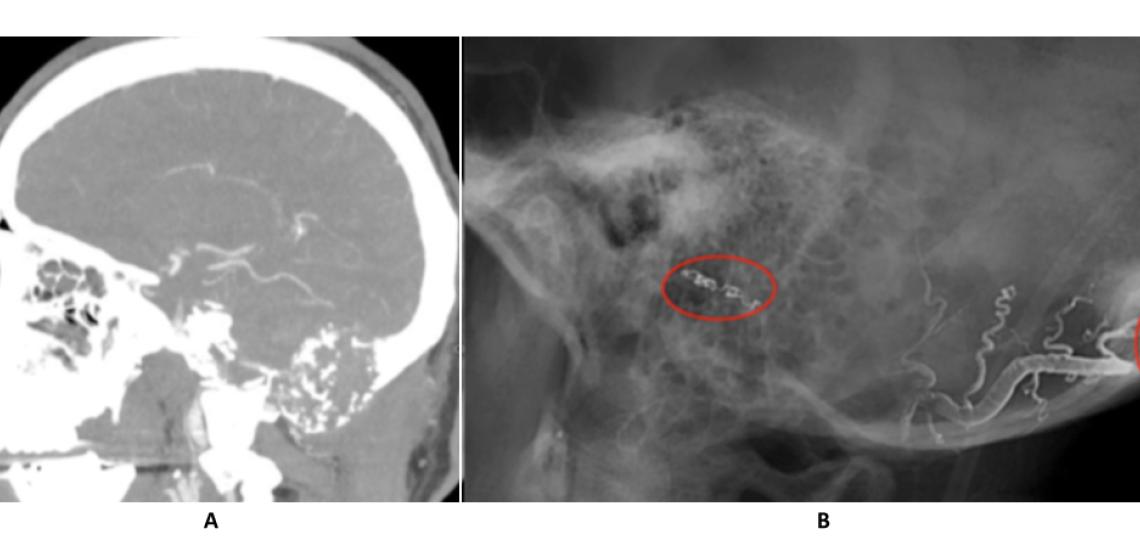

CT angiogram (A) reveals a large skull base tumor. Post-embolization angiogram (B) shows liquid embolics (onyx) in the feeding vessels supplying the tumor.